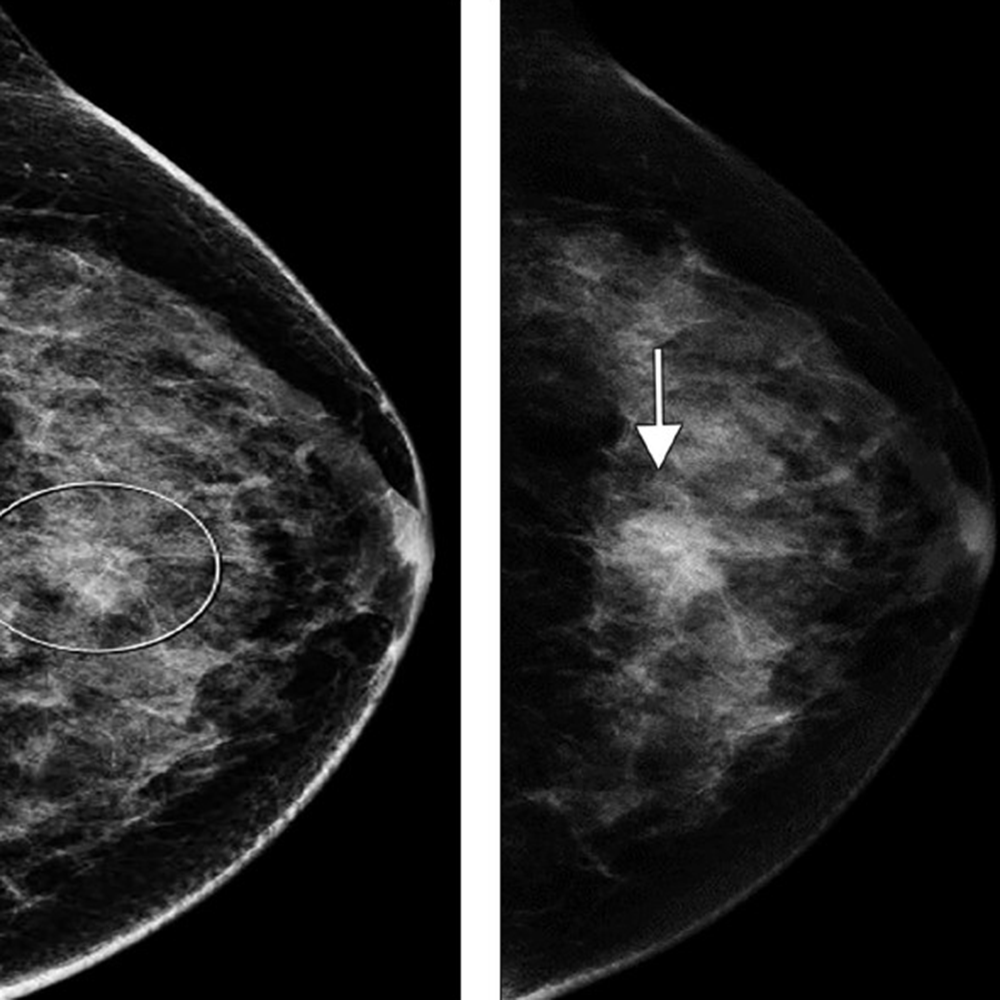

The latter mechanism most often results from strong muscular contraction that is unopposed by a counteracting fatigued muscle. In the case of rib stress fractures, the serratus anterior muscle plays a critical role [3, 4]. The serratus anterior muscle arises from the medial or ventral aspect of the scapula, with multiple slips extending anteriorly that attach to the first through tenth ribs at their middle third. The main role of the serratus anterior muscle is to protract the scapula. Importantly, this action is opposed by the scapular retractors (rhomboid muscles), which stabilize the scapula. In this situation, the serratus anterior muscle will promote an increase in the lateral diameter of the chest cavity. This mechanism can lead to abnormal stress at the middle third of the ribs in sports that involve repetitive contraction of the serratus anterior muscle, such as in elite rowing and swimming. In rowing, stress fractures are relatively common and may affect up to 12% of rowers. The peak contraction of the serratus anterior muscle occurs at the initial phase of the rowing cycle (known as “the catch”), in which the rowing oars are pulled away from the body, causing strong stabilization of the scapula by the rhomboid muscles and serratus anterior muscle. Performed repetitively, this action creates a compressive force vector directed toward the middle thirds of the ribs that can lead to stress fractures, most often affecting the fourth through eighth ribs in up to 86% of cases. If this compression is unopposed by a fatigued serratus anterior muscle, a repetitive stress injury may occur [3, 4]. Stress fractures also affect novice golfers who are still developing their technique and often strike the ground during swing strokes. Frequent ground impact force due to repetitive inaccurate strokes is thought to be transmitted to the chest wall on the leading side, causing stress fractures [5]. Additional sports in which rib stress fractures have been described include baseball, lacrosse, weightlifting, ballet, and gymnastics. MRI findings of rib stress fractures are similar to those seen in the extremities, including a well-defined linear area of low signal intensity surrounded by marrow edema, with the best contrast noted in T2- weighted fat-suppressed images (Fig. 1).

Edema in the surrounding intercostal muscles and extrapleural space is often noted [6]. As mentioned earlier, such fractures may be better depicted on oblique sagittal or coronal images that are tangential to the fracture and provide context, better showing rib portions adjacent to the fracture itself. Healing of rib stress fractures can be monitored by MRI, showing progressive improvement of marrow edema and bony bridging; however, clinical symptoms may persist even though the fracture appears healed on imaging.